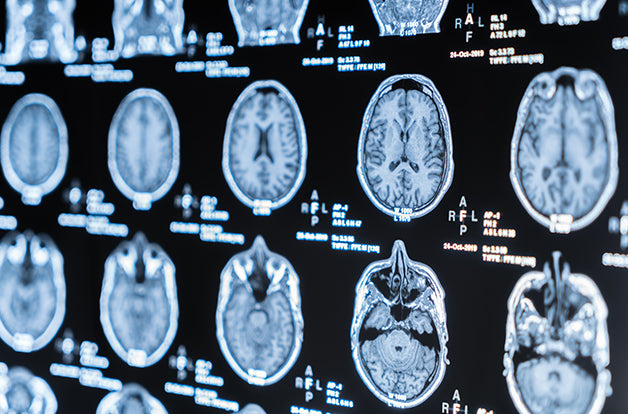

That’s in large part because neurological Lyme — also referred to as Lyme neuroborreliosis (LNB) — is often confused with other serious neurological conditions such as multiple sclerosis and Parkinson’s disease, which can be scary and overwhelming. And because most doctors lack an understanding of Lyme disease in general, and especially of Lyme associated with a predominance of neurological symptoms, LNB often goes unrecognized.

Symptoms of LNB are thought to occur from infiltration of white blood cells — immune cells like lymphocytes and plasmocytes — into the white matter of the brain and the spinal cord, otherwise known as the central nervous system (CNS). This is associated with an increase in inflammatory immune messengers, called cytokines, in cerebrospinal fluid.

Loss of sensory and motor nerve function is thought to be related to demyelination of nerve fibers. Found in the brain and peripheral nervous system, nerve fibers are coated with a fatty substance called myelin. Myelin acts much like the plastic coating on a copper wire: it wraps around nerve fibers, thus preventing the nerve fibers from touching each other and “shorting out” when an electrical current passes through. If demyelination is severe enough, it can result in abnormal nerve conduction tests, similar to multiple sclerosis.

Chronic Lyme disease shares many symptoms with other chronic illnesses. This is especially true of LNB and chronic neuroinflammatory illnesses such as multiple sclerosis, Alzheimer’s disease, amyotrophic lateral sclerosis (ALS), Parkinson’s disease, and traumatic brain injury (TBI).